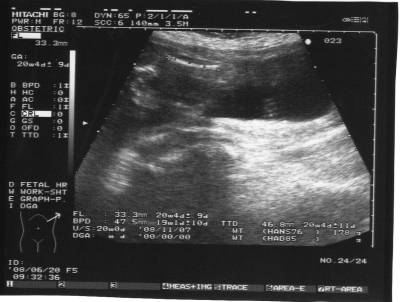

Megjöttem az uh-ról.

BPD: 4,3 cm

HC: 15,6 cm

AC: 13,6 cm

FL: 2,7 cm

OFD: 5,4 cm

Minden rendben vele, csak kicsit aggaszt, hogy a méhlepény hátsó fali, az alsó polusa eléri a belső méhszáj szélét.

Sajna nem tudták 100%-ra megmondani, hogy mi a neme. Az orvos szerint inkább kislány.

Szóval nem tudom, de szerintem nekünk se jött be a várvavárt nem.

4D -re augusztusban megyünk.

Naysa